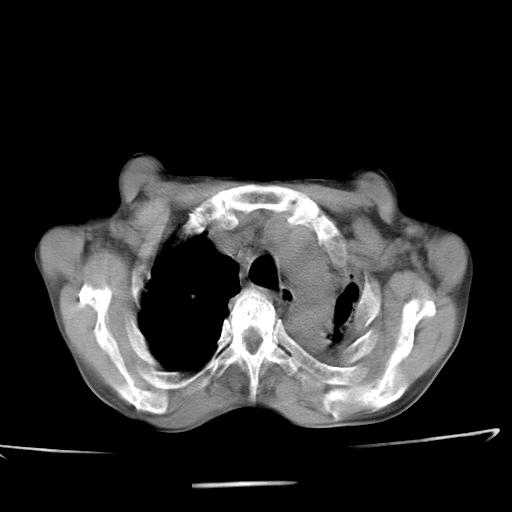

男  70岁,发烧咳嗽4天。盗汗,消瘦。无痰中带血丝,以前有肺tb病史,ct见,双肺tb,左侧胸廓塌陷,左胸膜肥厚粘连。纵隔移位,右侧胸腔积液,大家说说那个心影前左肺舌叶除了肺大炮还有炎症还是干酪性肺炎?有占位吗?我看纵隔淋巴结也大。

1)两肺继发性肺结核并左肺上叶肺不张,支气管扩张。2)双侧胸膜炎(胸膜增厚+少量胸腔积液)。

双肺继发性肺结核伴部分左肺毁损!

两肺继发性肺结核并感染,左肺上叶肺不张。建议ct增强。